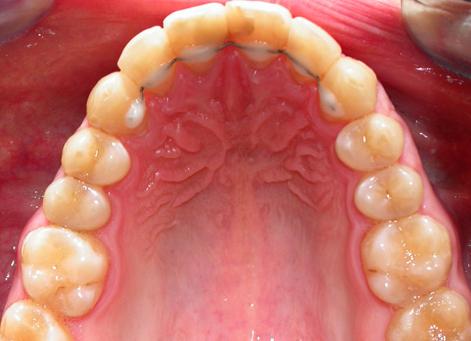

Лечение проводилось с апроксимальной сепарацией эмали зубов. Применялись керамические брекеты.

Результат получен спустя 18 месяцев после начала лечения